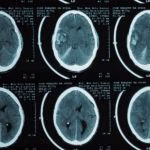

- Traumatismo craniano

- Hematoma cerebral

- Fratura do crânio

- Hematoma extradural

- Contusão cerebral traumática